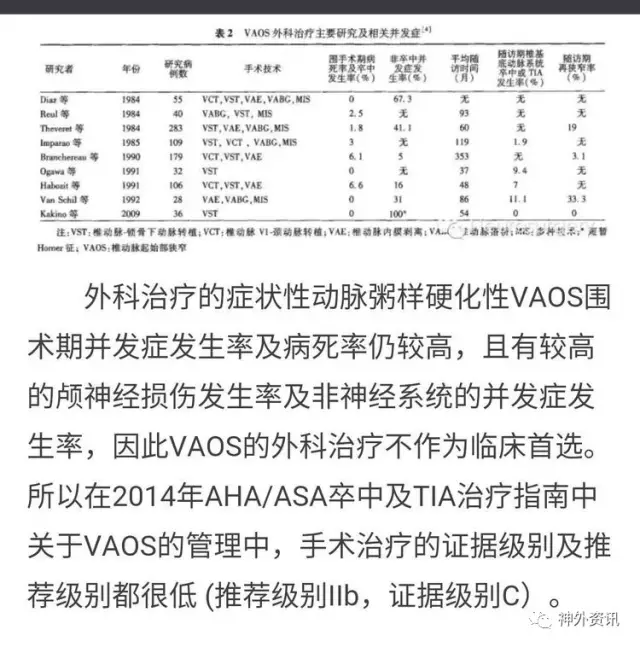

2014版VA狭窄指南:文献提示VA支架后再狭窄达11-30%,所以VA内膜剥脱术对于症状性闭塞和狭窄还有技术应用的空间。

2014版VA狭窄指南:外科治疗VA狭窄并非一线干预方法,但我们可以给支架植入失败和症状性支架内再狭窄或闭塞患者提供终极治疗方案,面对病人我们应当提供序贯性的治疗,天下大同,内外一家,解决的病人疾病之苦痛。